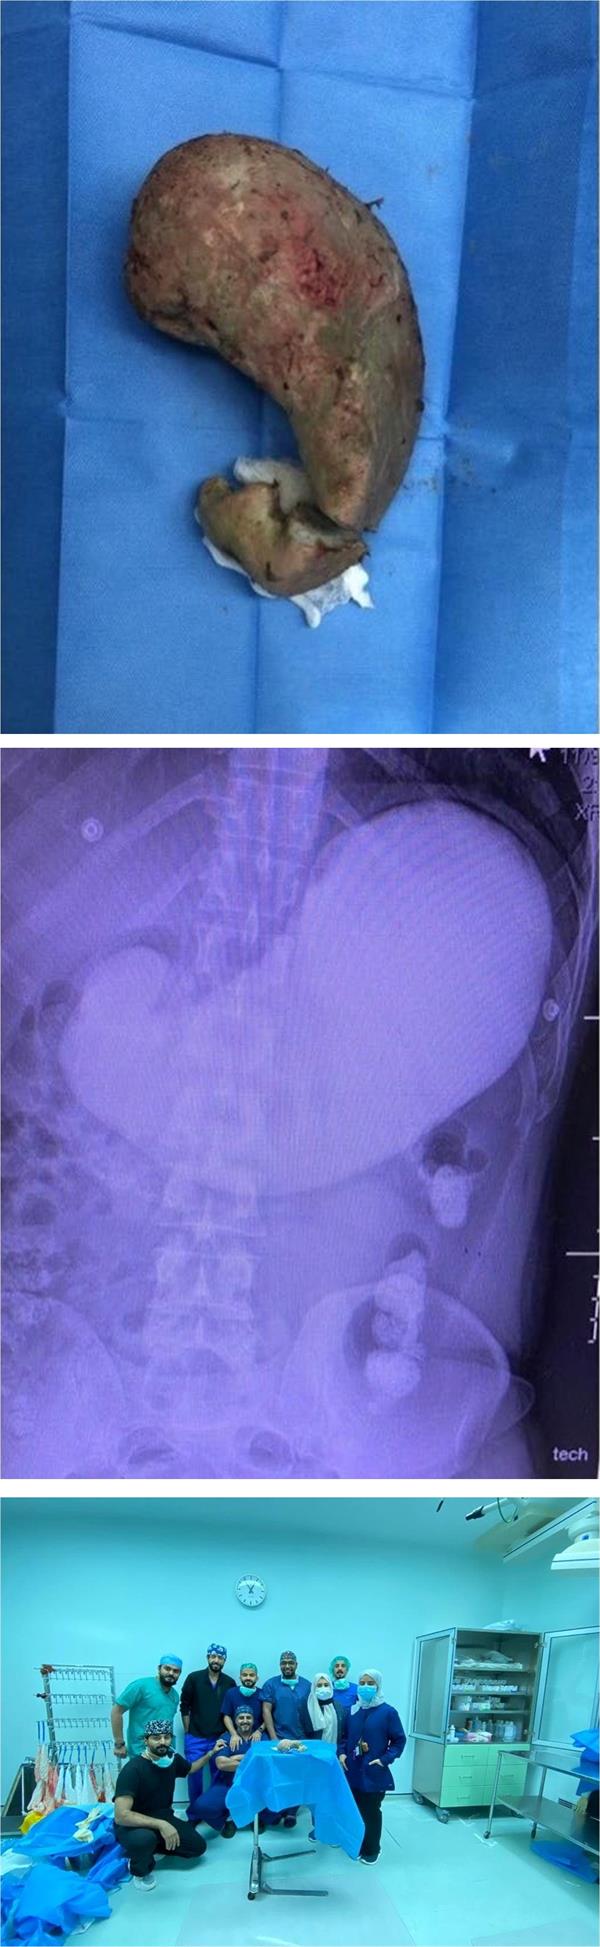

وأوضحت المديرية العامة للشؤون الصحية بجدة، أن الخليط الأسمنتي تجمد داخل معدة المقيم وأدى إلى انسداد تام فيها مع تسببه في آلام حادة له بمنطقة البطن.

وبينت أن الفريق الطبي بمستشفى الملك عبد العزيز الذي باشر الحالة أدخله إلى الفور إلى غرفة العمليات، واستخرج الجسم الأسمنتي المتجمد من معدته مع إصلاح الأضرار التي طالت نسيج المعدة.

وأشارت إلى أن العملية استغرقت نحو 3 ساعات، وأن المريض حالياً بصحة جيدة ووضعه مستقر.